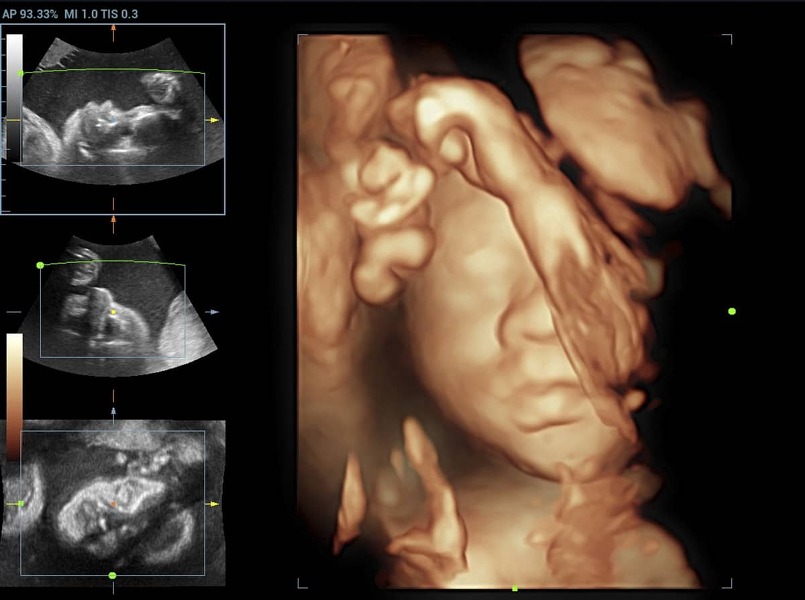

Pri rozšírenom morfologickom, genetickom ultrazvuku sa navyše sleduje profil tváre (ústa, pery, nos), jednotlivé časti mozgu, stav dôležitých ciev a ich prietoky, podrobne sa vyšetruje bránica a srdce, využíva sa 3D/4D zobrazenie. Pri vyšetrení sa zámerne vyhľadávajú anomálie, ktoré môžu svedčiť o závažnej vývojovej vade.

2D, 3D alebo 4D ultrazvuk

„Povinné“ prenatálne ultrazvuky sa robia 2D formou, stačí to na zistenie všetkých potrebných údajov, ktoré lekár potrebuje zistiť o plode. Ide o hlavný diagnostický nástroj pri ultrazvukovom vyšetrovaní. 3D ultrazvuk predstavuje statické zobrazenie plodu, avšak v priestore. Trojrozmerný obraz sa dosahuje počítačovým spracovaním súboru nakumulovaných 2D obrazov. Ďalšou môžnosťou je 4D zobrazenie, ktoré sa od plastického 3D obrazu líši jedným faktorom navyše – časom/pohybom. Snímku vidíte v priamom prenose, môžete sledovať, ako sa dieťa hýbe a sledovať jeho mimiku. 3D a 4D ultrazvuky nie sú bezplatné.